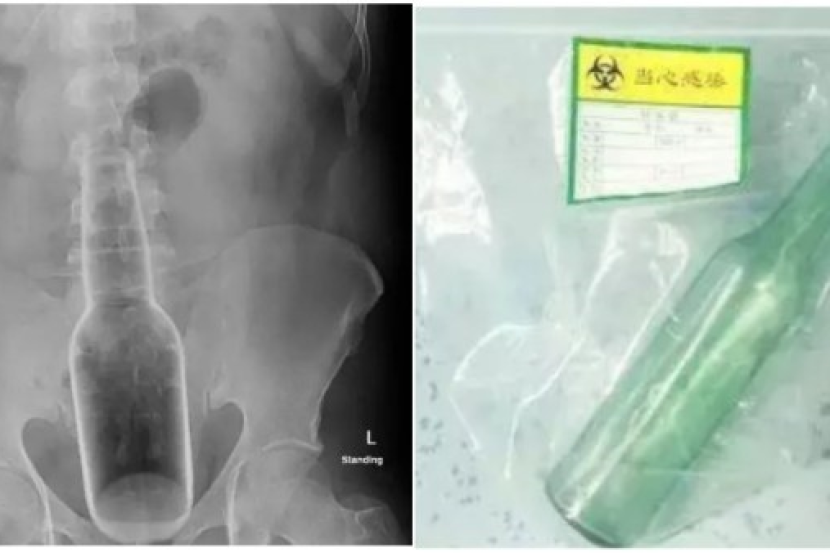

Pemeriksaan lanjut mendapati botol kira-kira enam sentimeter tersangkut di bahagian bawah tubuhnya.

Pakar Gastroenterologi, Dr Lin Jun telah menjalankan pembedahan dubur di hospital di wilayah Guangdong, selatan China.

"Keseluruhan botol itu berada dalam rektumnya," katanya.

Menceritakan lebih lanjut, kata warga emas itu, botol Florida Water itu dengan tidak sengaja masuk menerusi rektum nya ketika dia menggaru-garu bahagian itu.